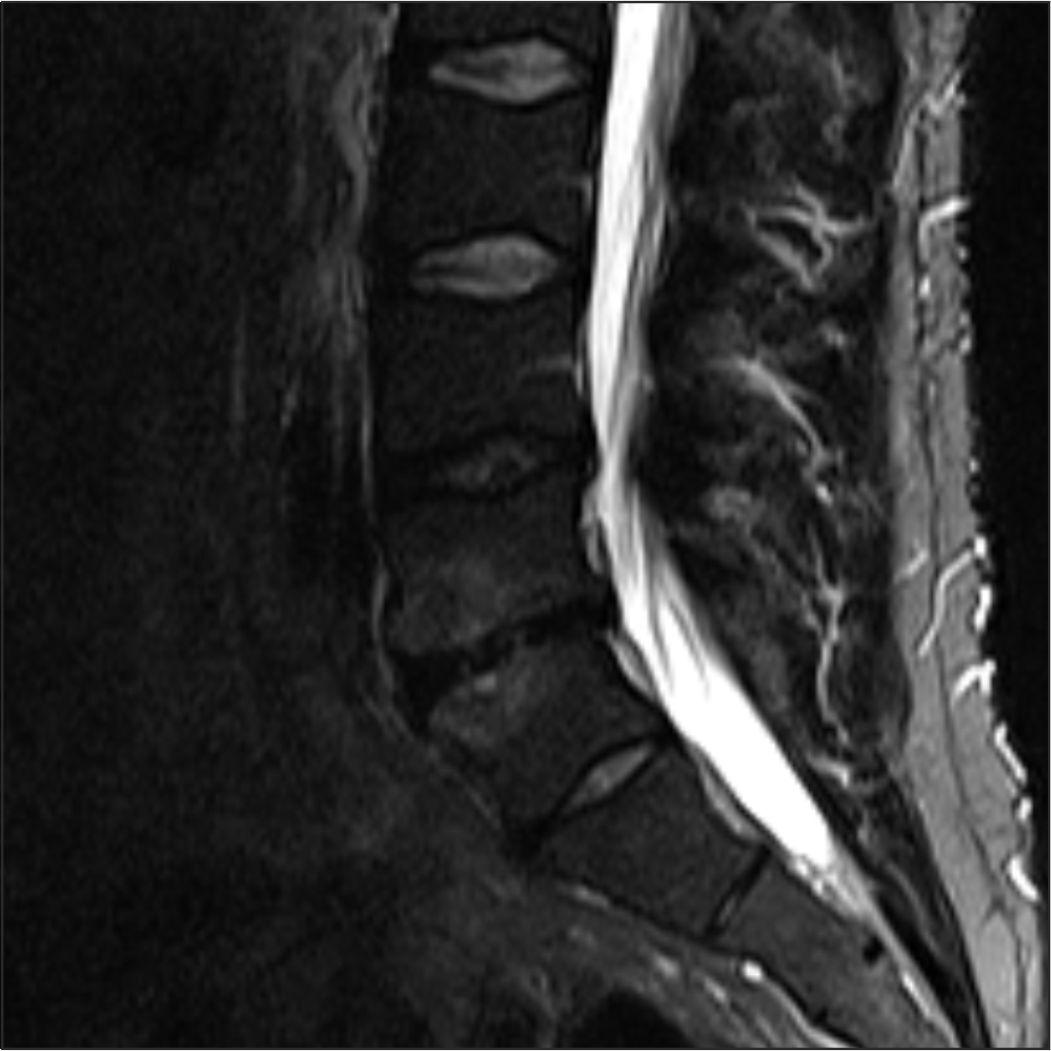

енение по типу modic 1